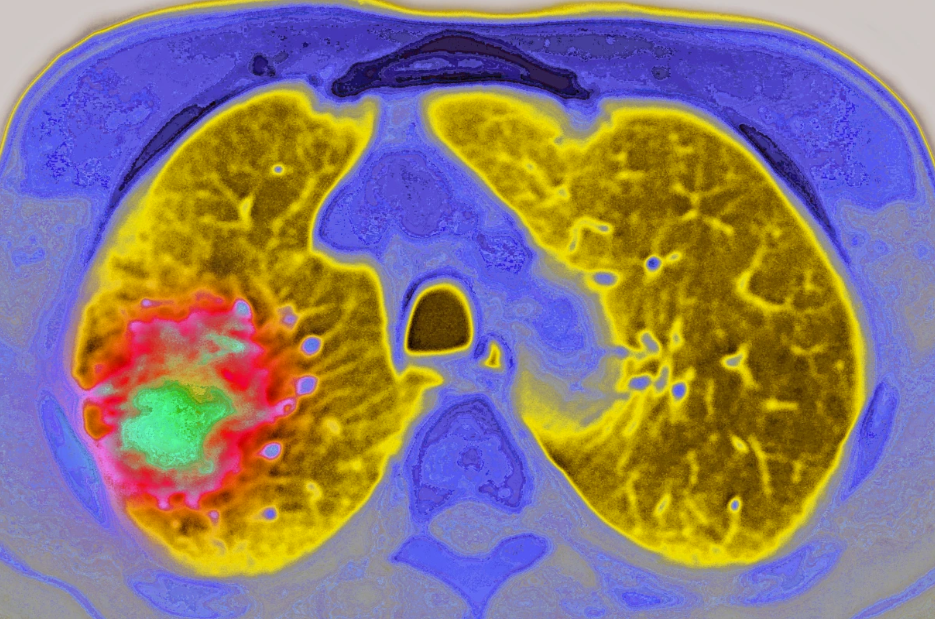

肺癌案例

Our cases

肺癌四期患者:我在美国丹娜法伯如何实现无癌生存

导读:从巅峰跌入低谷,一位热爱运动的女性凭借坚韧不拔的精神,在丹娜—法伯癌症中心的帮助下,勇敢面对肺癌治疗。如今,她不仅为自己而战,更激励他人,通过慈善机构传递正能量,证明癌症无法定义她的人生。美联医邦作为拥有9年出国看病服务经验的美国本土的高端医疗咨询机构,像大家介绍一位在丹娜法伯癌症研究所的治疗肺癌之路,感受EGFR抑制剂疗法为肺癌四期患者带来的无限希望与可能。关键词:肺癌四期;丹娜法伯癌症研